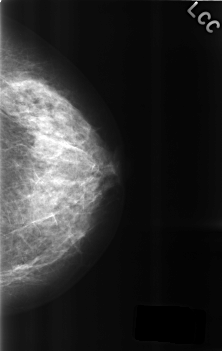

C_0308_1.LEFT_CC

LEFT_CC LINES 4552 PIXELS_PER_LINE 2880 BITS_PER_PIXEL 12 RESOLUTION 50 NON_OVERLAY